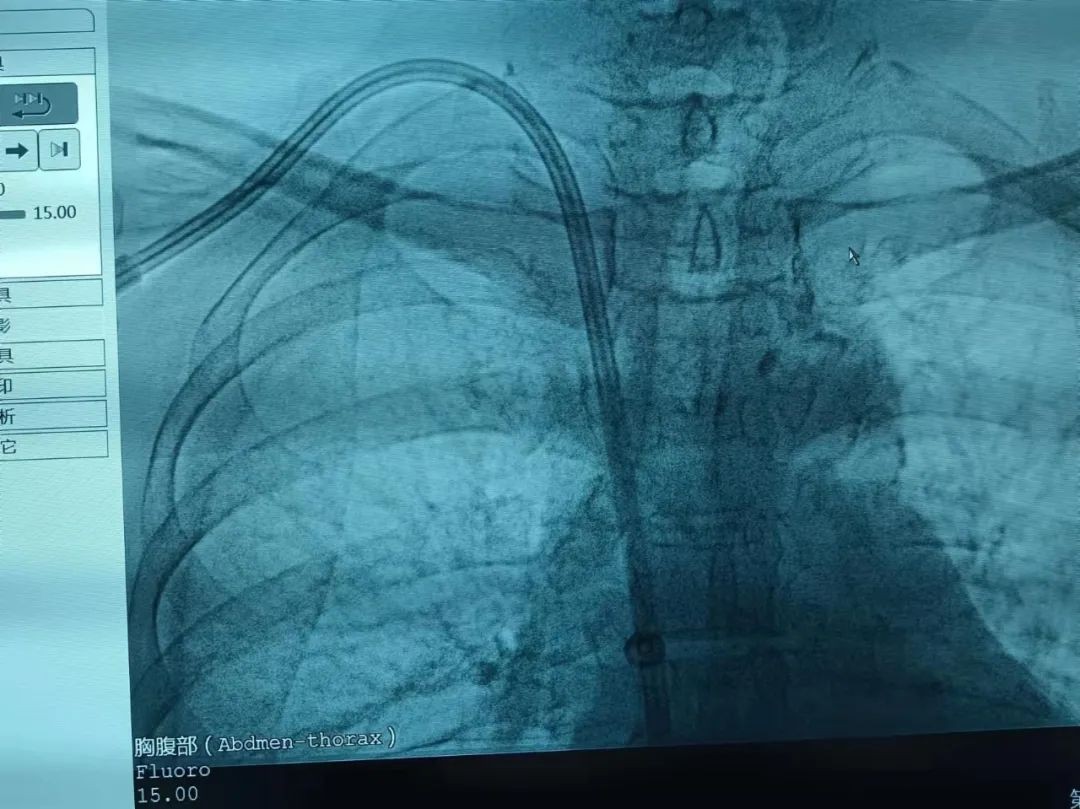

术前体表定位,DSA下确认位置。消毒铺巾,撤除临时导管,超声引导下给予后路穿刺,置入导丝、血管鞘,于拟定导管出口处切开皮肤1.5cm,穿刺处切开皮肤1.5cm,建立皮下隧道并引入导管,分别置入扩张器、撕脱鞘,沿撕脱鞘置入导管,造影显示准确置入TCC,导管上段弧度良好,导管尖端准确置于右心房。该患者行DSA引导下TCC置入术,手术顺利未出现出血等手术相关并发症及静脉阻塞症状,充分证实了DSA引导下穿刺置管的高效安全。

以前在没有介入室的支撑下,行TCC置入,存在误穿动脉、导管尖端位置不理想等缺点,明显增加了导管功能不良及中心静脉狭窄的发生率。因此,德州市中医院血液透析中心对传统的TCC置入术进行了改进,采用DSA引导,完成长期透析导管置入,为提高一次穿刺成功率提供了有力保障,置管完成后还可以对透析导管尖端所在部位有明确了解,并在DSA下直接调整,确保导管尖端位于右心房,避免非DSA引导下置管不到位时反复手术调试,减少血管损伤,降低2次穿刺率,降低穿透血管壁等出血风险和意外发生。